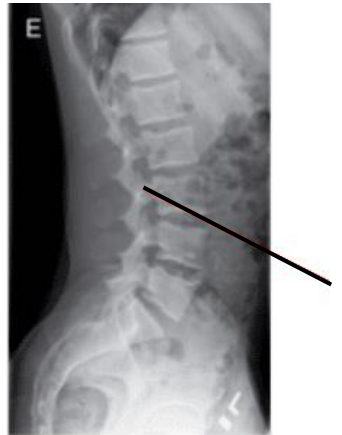

A imagem radiográfica abaixo demonstra qual detalhe anatômico: